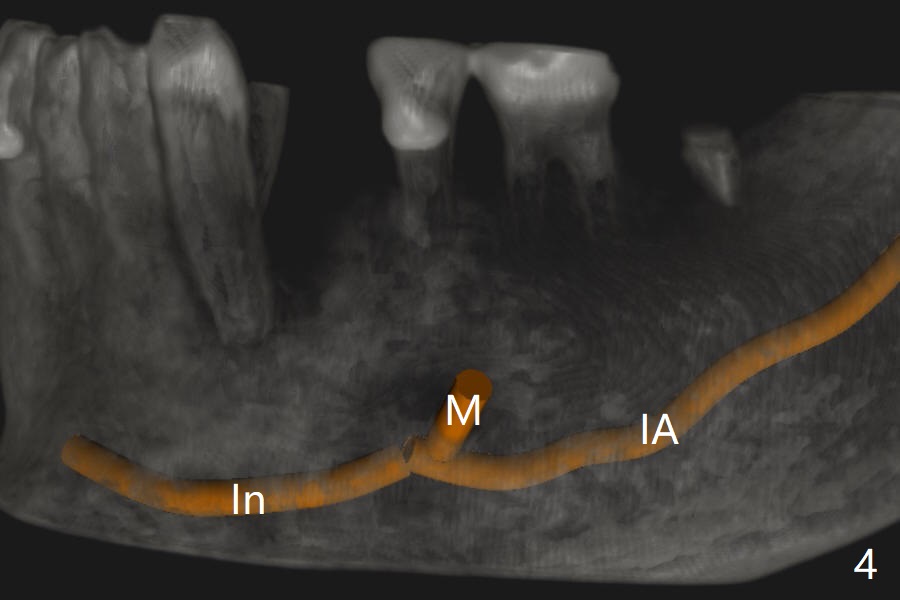

A 75-year-old man requests implant placement at #21 several years after traumatic extraction (Fig.1) with the narrow ridge (Fig.2). After ridge reduction ~ 3.5 mm (Fig.1,3), a 3.5x11 mm implant will be placed to avoid the Incisive canal (In in Fig.1,4) and the Mental Loop (M). In fact the patient agrees to have guided surgery and then changes mind.